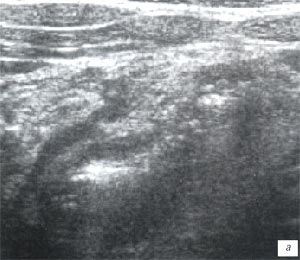

При УЗИ органов брюшной полости в правой подвздошной области и/или несколько выше (паракавально) определялись лимфоузлы с воспалительными изменениями, которые выглядели как единичные или множественные (часто - конгломерат) неправильно-округлой формы образования с ровными, четкими контурами, пониженной эхогенности (рис. 4 а-г). Максимальные размеры лимфоузлов у детей при банальном мезадените достигали 25-28 мм. Обычно в конгломерате имелось 2-3 крупных лимфоузла, к которым прилежали многочисленные более мелкие.

Острое воспаление лимфоузла проявлялось изменением его формы (он становился более округлым) и диффузным понижением эхогенности, при допплеровском исследовании определялась гиперемия лимфоузлов в виде усиления сосудистого рисунка со снижением резистивного индекса артериального кровотока до 0,6 и ниже. По мере стихания остроты воспалительного процесса эхогенность лимфоузлов повышалась, форма становилась уплощенной, лимфоузлы постепенно (недели, иногда - месяцы) уменьшались в размерах и исчезали. Эхографические изменения, расцениваемые как проявления острой воспалительной трансформации лимфоузлов (округлой формы, гипоэхогенные, чаще - более 10-14 мм в диаметре в зависимости от возраста ребенка), клинически проявлялись абдоминальным болевым синдромом, по мере стихания воспалительных изменений (плоские лимфоузлы средней эхогенности) субъективных жалоб дети не предъявляли. В одном случае абдоминальный болевой синдром у ребенка был вызван инородным телом двенадцатиперстной кишки с развитием эрозивного гастродуоденита, мезаденита. Обнаружение инородных тел линейной формы при УЗИ представляет собой большую сложность и возможно только при тщательном полипозиционном сканировании (рис. 4 д-з).

а, б) Исследование в В-режиме и допплеровское сканирование в энергетическом режиме при мезадените. Ребенок, 6 лет. Определяется конгломерат гиперемированных лимфоузлов пониженной эхогенности.